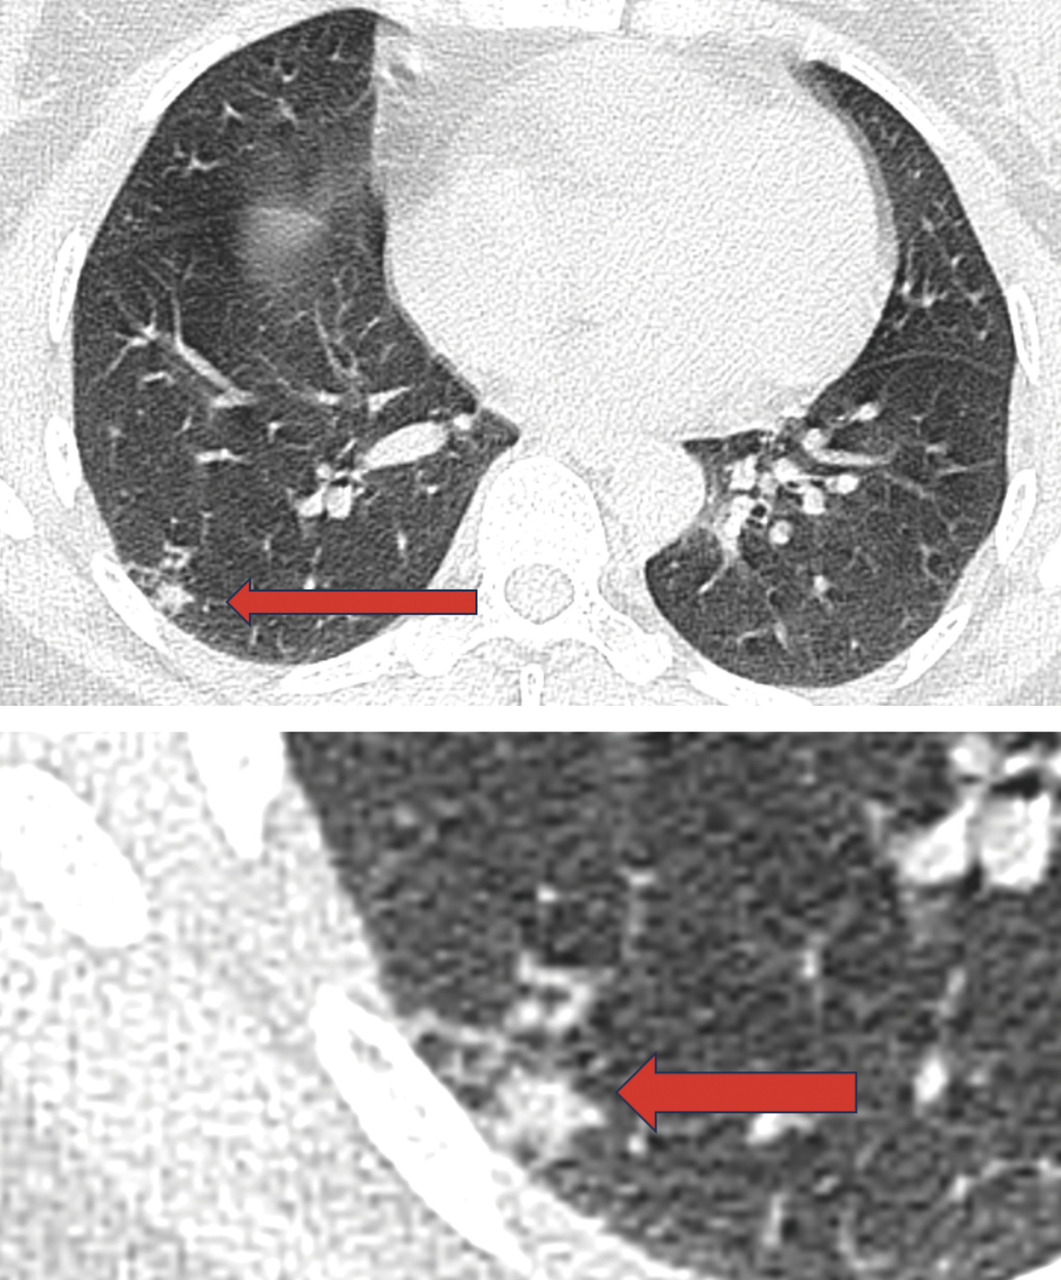

Un scanner cervico-thoraco-abdomino-pelvien est réalisé, à la recherche de signes radiologiques d’une pathologie associée. Il montre des adénopathies médiastino-hilaires droites, nécrotiques (fig. 2) et un foyer de micronodules parenchymateux pulmonaires lobaires inférieurs droits, confluents, avec un nodule central, réalisant le signe de la galaxie, visible sur une tomodensitométrie axiale du thorax (fig. 3). Ces signes sont-ils ceux d’une sarcoïdose pulmonaire active ou d’une atteinte granulomateuse de type tuberculose ou d’une autre cause ?